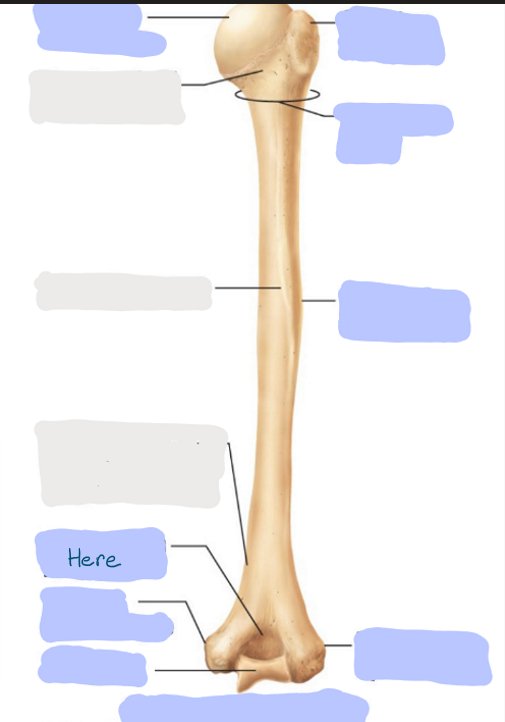

What is this picture of?

Anterior view of the right humerus

What is here?

Where is the Head of the humerus?

What is here?

Where is the Greater Tubercle of the humerus?

What is here?

Where is the Lesser Tubercle of the humerus?

What is here?

Where is the Intertubercular Sulcus of the humerus?

What is here?

Where is the Deltoid Tuberosity of the humerus?

What is here?

Where is the Capitulum of the humerus?

What is here?

Where is the Trochlea of the humerus?

What is here?

Where is the Medial Epicondyle of the humerus?

What is here?

Where is the Coronoid Fossa of the humerus?